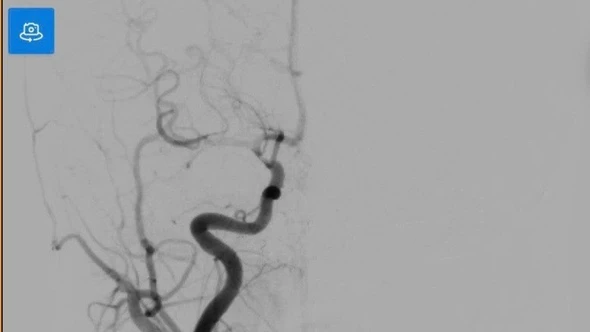

Mường Khương từng là "vùng trũng" về tiếp cận dịch vụ y tế chuyên sâu, tuy nhiên hiện nay những bước tiến của y học địa phương đang lặng lẽ tạo nên kỳ tích. Tại Trung tâm Y tế khu vực Mường Khương, các y, bác sĩ đã làm chủ kỹ thuật khai thông mạch não bằng điều trị thuốc tiêu sợi huyết - kỹ thuật loại đặc biệt đòi hỏi chuyên môn cao và sự phối hợp khẩn trương trong từng phút giây vàng.